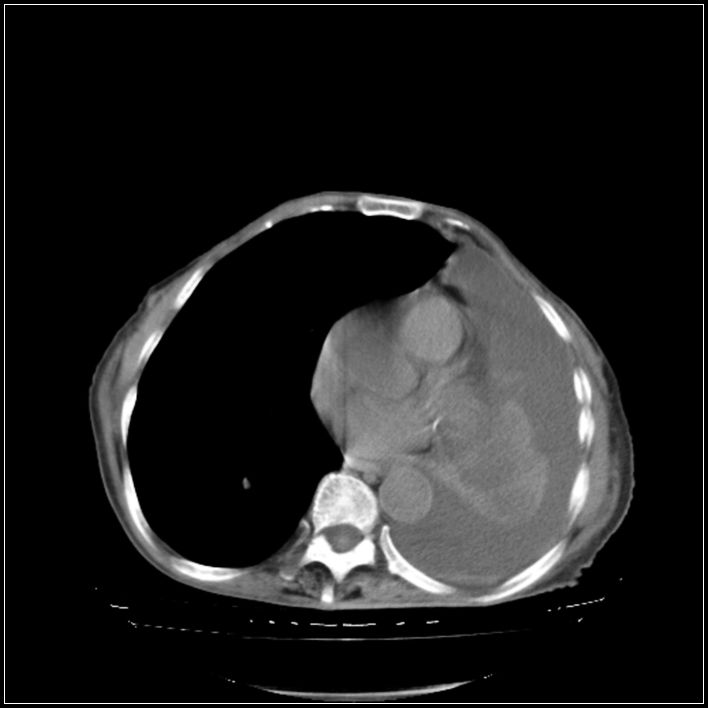

以下是引用影象小辈在2008-5-31 16:25:00的发言:[br]左侧胸腔团状不规则致密影,界欠规整,密度不均匀,其内可见更低密度影及高密度影,并可见包裹性胸腔积液 考虑为1.畸胎瘤 2.肺癌